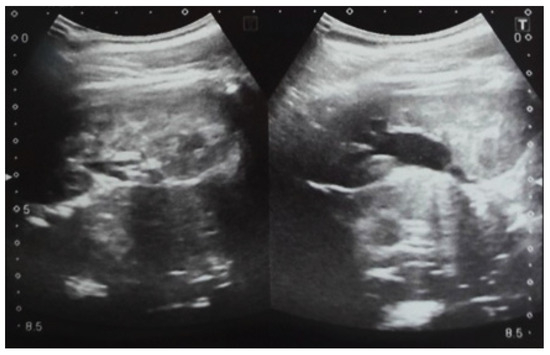

Our experience with congenital malformations of the urinary system refers to the following clinical case (Figure 2, Figure 3, Figure 4, Figure 5, Figure 6, Figure 7, Figure 8 and Figure 9). In the first case, during pregnancy, the 21-week ultrasound determined bilateral renal pyelectasia. The fetus had hydronephrosis on the right; at 31 weeks, it had bilateral hydrocalconephrosis; and at 32 weeks, bilateral pyelectasia. It suffered premature birth at 36 weeks, with complicated anomalies of the forces of contraction, prolonged birth, and birth weight of 2200 g. Postnatal ultrasonography was supplemented by intravenous urography, and bilateral hydronephrosis was determined. Hydrocalconephrosis on the left was discovered. The complete diagnosis was established: congenital renal malformation; bilateral pyelectasia; bilateral hydronephrosis; hydrocalconephrosis on the left; and severe reduced glomerular filtration rate (GFR), GFR > 2SD below mean.

Figure 2. Intrauterine ultrasound at the 21st week of pregnancy. Ultrasonography—the fetus corresponds to the age of 20–21 weeks. Bilateral renal pyelectasia.

Figure 3. Ultrasound at the 20th week of gestation. Hydronephrosis on the right. (1) Dilated pelvis on the right. (2) Uninjured renal parenchyma on the left.